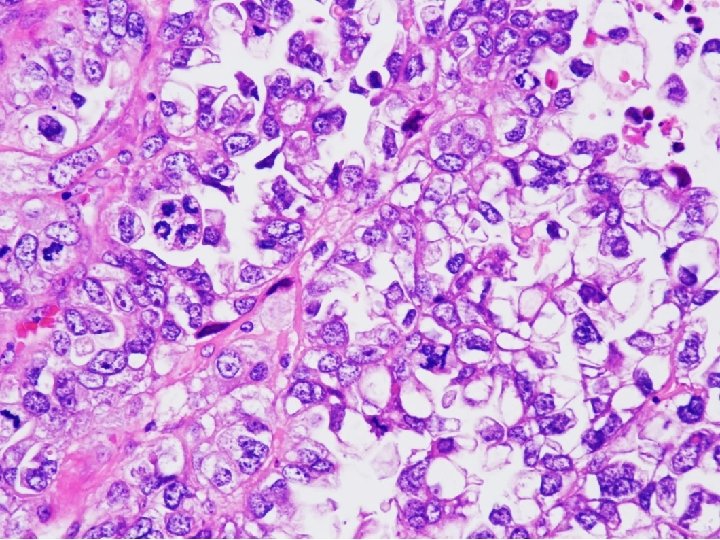

Tissue from uterine cervix, biopsy; Poorly differentiated adenocarcinoma with 1) sheets and papillary features 2) tubulocystic pattern 3) frequent clear cell feature c/w CLEAR CELL CARCINOMA

• Clear cell carcinomas present marked cellular and nuclear pleomorphism; they often have bizarre nuclei and abundant, pale cytoplasm Color Atlas of DDx in Exfoliative and Aspiration Cytopathology, Kini

CYTOPATHOLOGIC FEATURES OF CLEAR CELL CARCINOMA • Arrangement – Cells are isolated, in loosely cohesive groups and in syncytial tissue fragments; hobnail pattern may be present • Cells – Medium to large with poorly defined cell borders; moderate to high N/C ratios; round, polygonal to hobnail type • Nuclei – Large, round, often eccentric, very pleomorphic; coarsely granular to smudgy chromatin; nucleoli are inconsistent; multinucleation • Cytoplasm – Variable, scant to abundant, clear to pale, weakly staining either eosinophilic or cyanophilic • Background – Clean, bloody or inflammatory; naked nuclei Color Atlas of DDx in Exfoliative and Aspiration Cytopathology, Kini